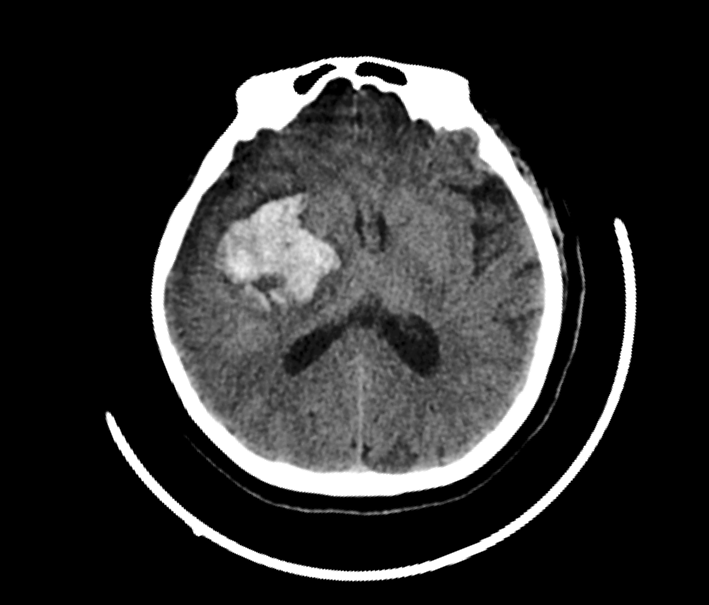

(下图左为患者术前出血照片,右为术后照片)

近日,一名年轻女性患者突发头痛加剧至昏迷不醒,紧急来白银市中心医院就诊。经检查,患者右侧基底节区脑出血,而且出血量较大,情况十分危重。神经外科主任杨永春当即带领医疗团队争分夺秒地为患者进行手术,展开了一场与死神之间的“生命保卫战”......最终患者病情得到了初步控制。

“但患者凝血功能不好、持续出血,血压控制并不理想,危险随时可能发生,必须准备二次手术。”杨永春事后回忆道“虽然二次手术难度很大,但大家齐心协力,在省上专家的远程指导下,我们抓住最佳手术时机,最终顺利完成了手术。”手术虽然成功了,但两次手术后愈合和恢复情况依然不乐观,患者转入ICU病房继续治疗。